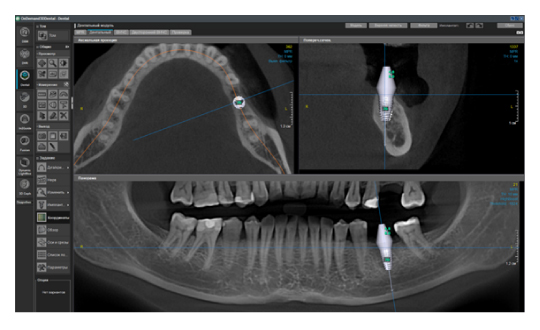

Ещё одна актуальная проблема в современной стоматологии — это огромное количество разных программ просмотровщиков конусно-лучевой компьютерной томографии. Каждый производитель этого ПО старается сделать что-то уникальное, и для конечного доктора это порой усложняет диагностику. Вы привыкли работать в одной программе, а тут уже пришел пациент с КЛКТ исследованием в совершенно незнакомом софте. У меня даже существует отдельный курс по разбору разных программ, чтобы врач всегда мог сориентироваться и провести консультацию. Но если вы решили купить собственный дентальный томограф, то здесь совет брать программу, которая технически удовлетворит все ваши запросы. Стоит помнить о том, что если вы будете проводить исследования не только для нужд своей клиники, но и сторонним, то эта программа не должна быть обрезанной по функционалу, являться простой, русифицированной, а также знакомой и понятной многим. От себя хочу добавить, что советую обращать внимание на возможность использования различных фильтров резкости изображения, изменения толщины среза, возможность построения произвольных кросс-секций на панорамном реформате, а также большой базы имплантатов (рис. 5), и чтобы всё это было доступно не только в лицензии, но и во viewer (просмотровщике, который получает конечный врач).

Критерии выбора конусно-лучевого компьютерного томографа.-08 (1).jpg

Рис. 5. Пример программы OnDemand3D. Панорамный реформат с повышенным фильтром резкости, произвольной кросс-секцией, установленным виртуальным имплантатом.